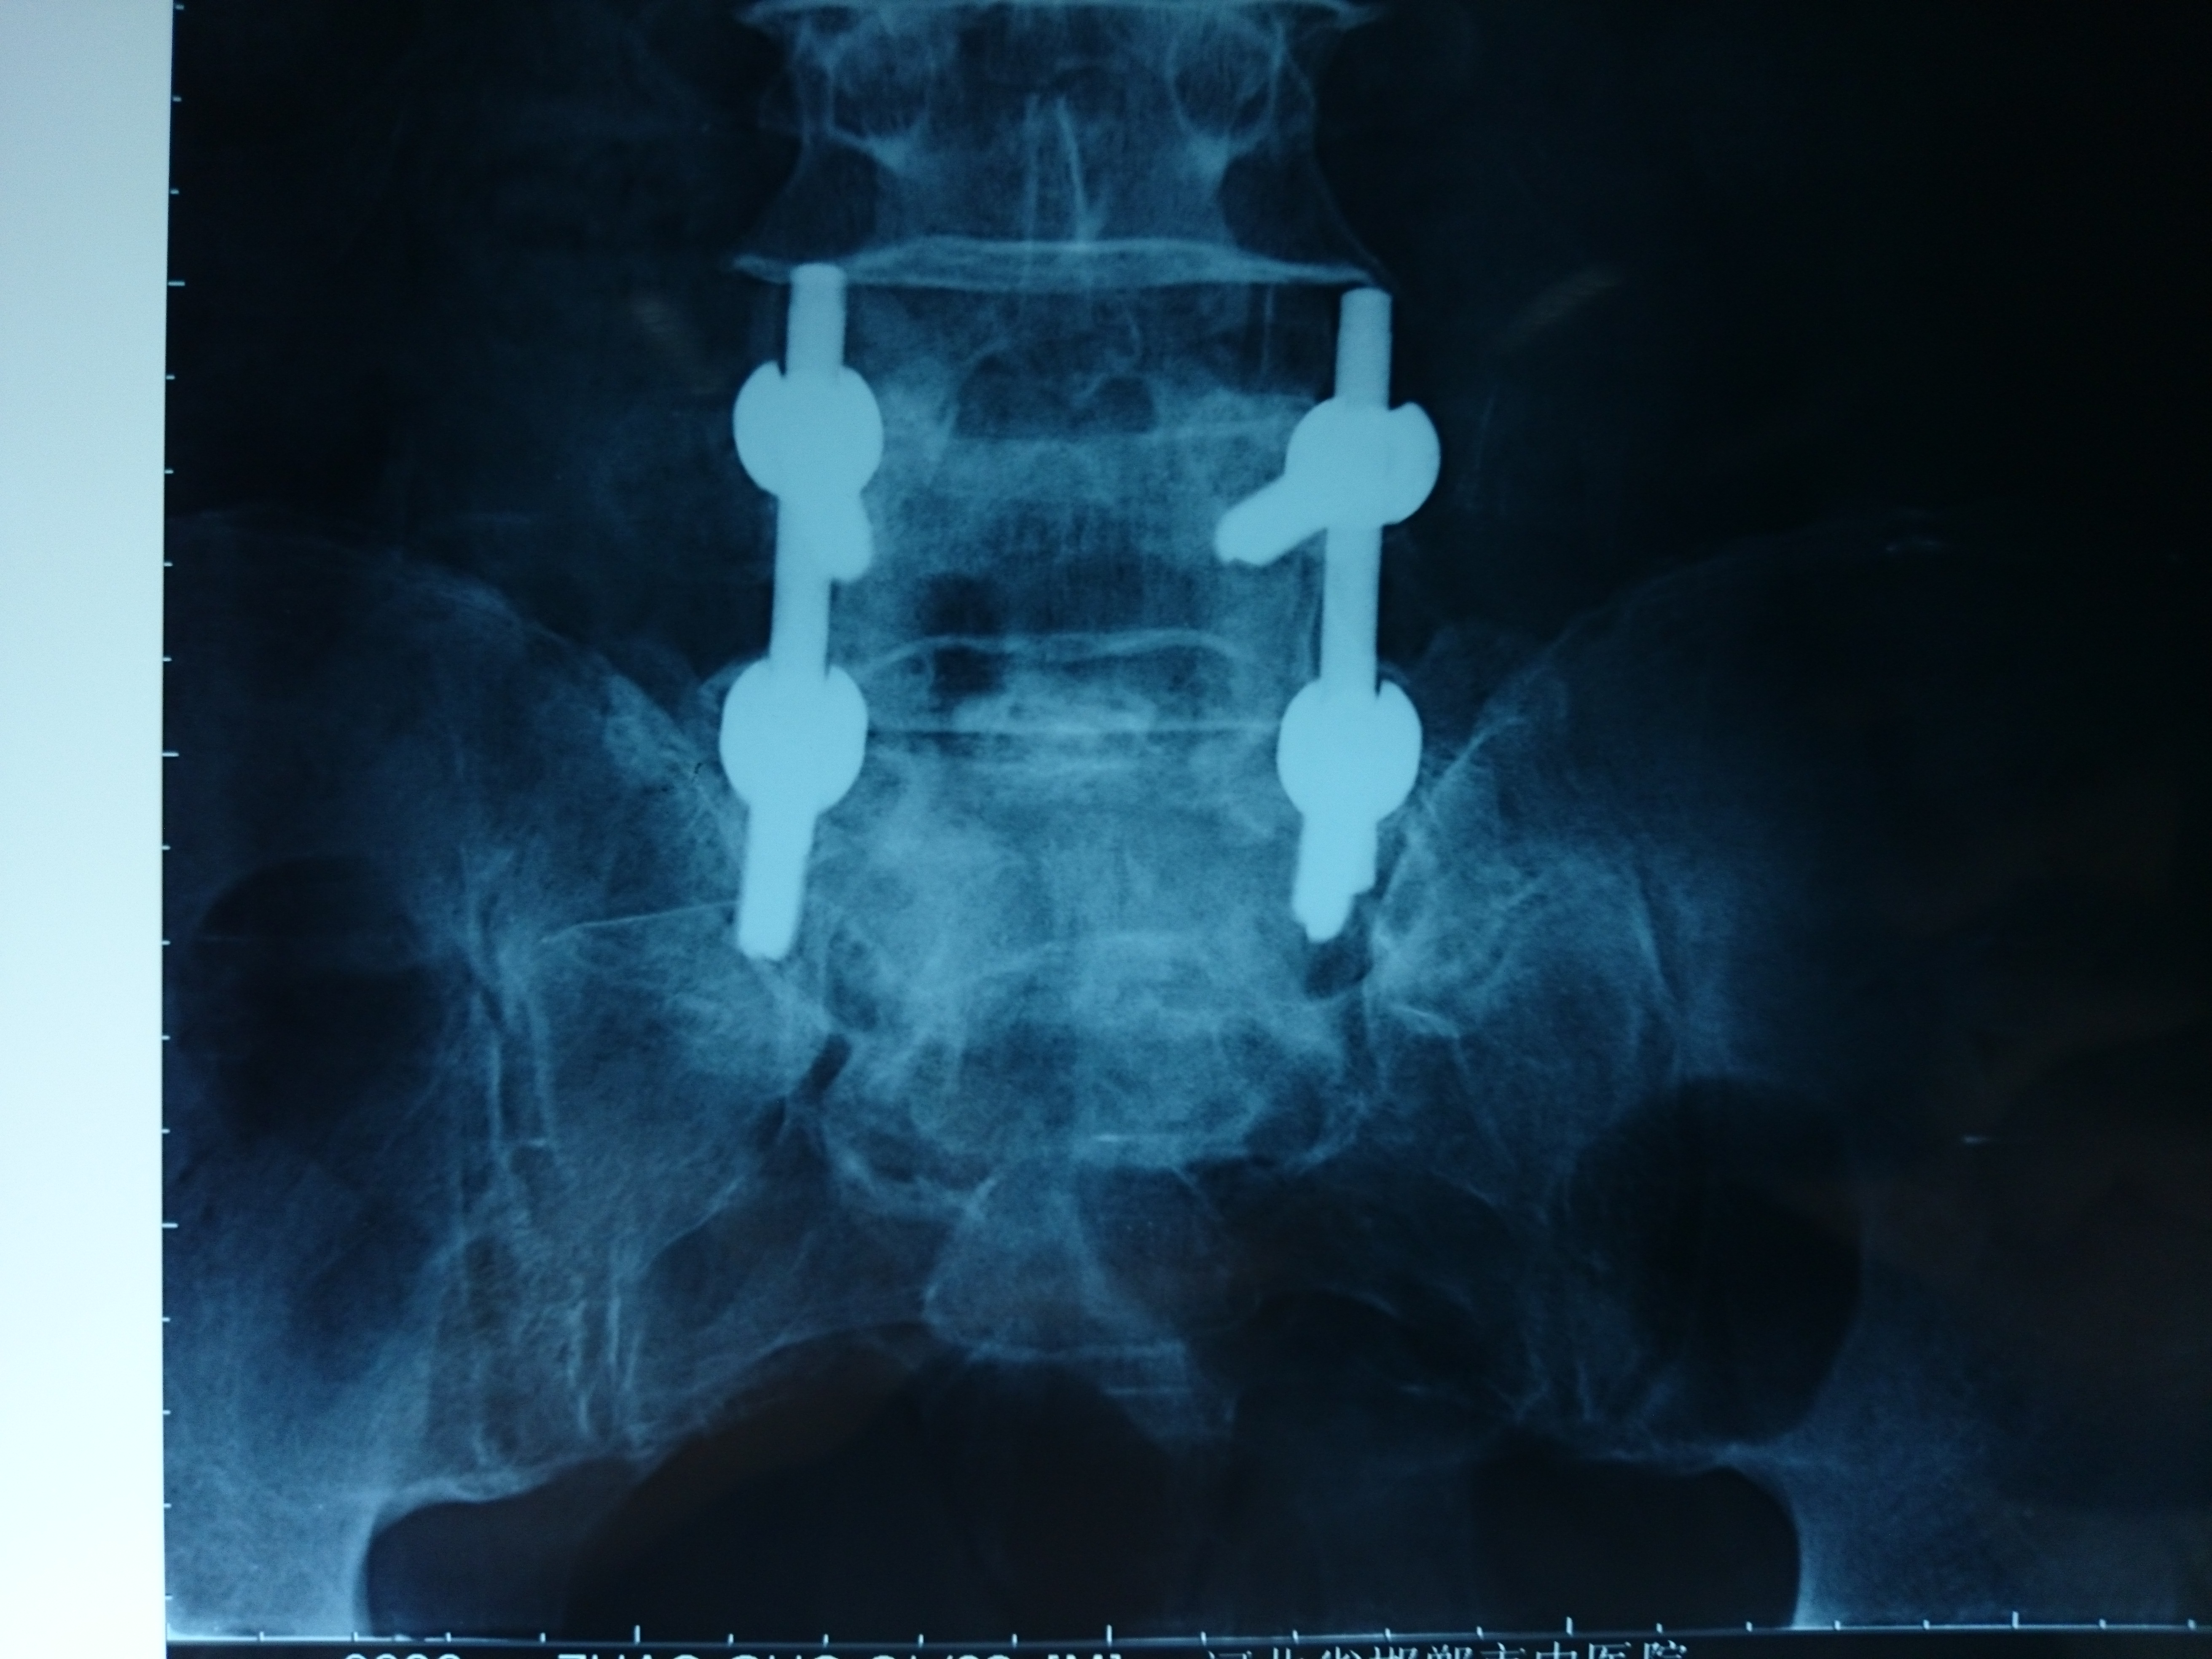

首页 > 张恒云工作室 > 影像资料 三十四